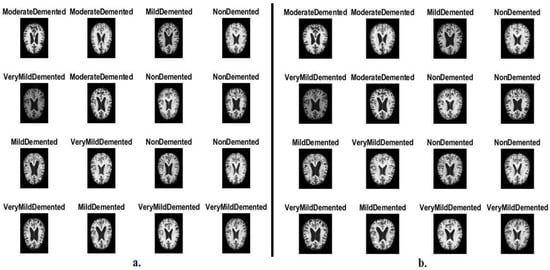

3.1. Description of the MRI Dataset

3.4. Data Augmentation and Balancing Dataset